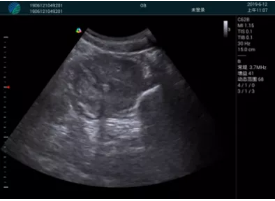

頸動(dòng)脈血流充盈飽滿,無外溢

肝內(nèi)血管顯示清晰,血流敏感無外溢

甲狀腺囊性結(jié)節(jié),囊壁鈣化,透聲好

甲狀腺囊性占位